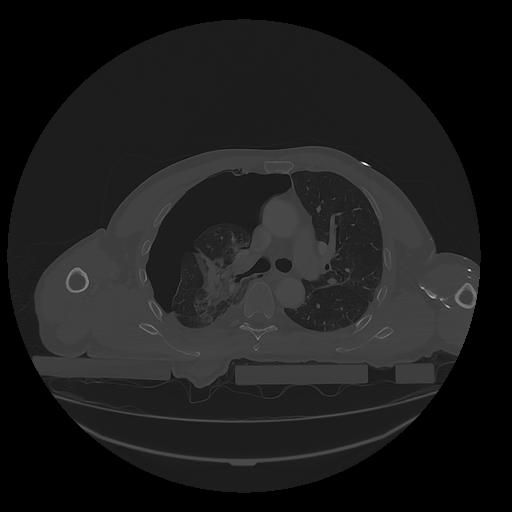

31 PULMON,CE,Vol,1.0,PULMON,,